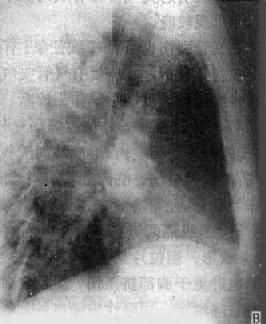

2)右肺中叶不张:较为常见,后前位表现为右肺下野内侧靠心右缘现上界清楚下界模糊的片状致密影,心右缘不能分辨(图3-1-9)。侧位上表现为自肺门向前下方倾斜的带状或尖端指向肺门的三角形致密影(图3-1-9)。上、下叶可有代偿性肺气肿。

图3-1-9 右肺中叶肺不张(正、侧位)